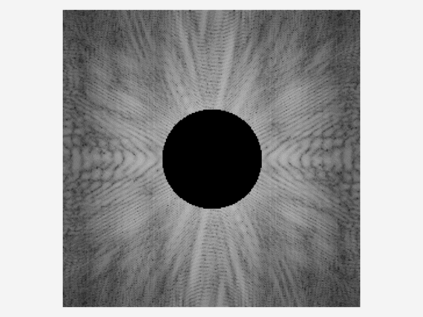

Reconstructing magnetic resonance (MR) images from undersampled data is a challenging problem due to various artifacts introduced by the under-sampling operation. Recent deep learning-based methods for MR image reconstruction usually leverage a generic auto-encoder architecture which captures low-level features at the initial layers and high?level features at the deeper layers. Such networks focus much on global features which may not be optimal to reconstruct the fully-sampled image. In this paper, we propose an Over-and-Under Complete Convolu?tional Recurrent Neural Network (OUCR), which consists of an overcomplete and an undercomplete Convolutional Recurrent Neural Network(CRNN). The overcomplete branch gives special attention in learning local structures by restraining the receptive field of the network. Combining it with the undercomplete branch leads to a network which focuses more on low-level features without losing out on the global structures. Extensive experiments on two datasets demonstrate that the proposed method achieves significant improvements over the compressed sensing and popular deep learning-based methods with less number of trainable parameters. Our code is available at https://github.com/guopengf/OUCR.